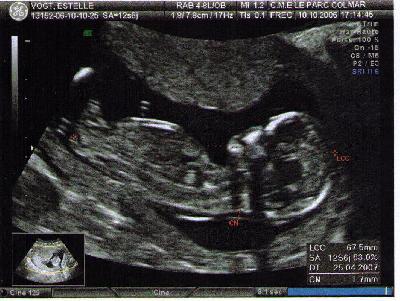

Dans le ventre de sa maman

• échographie

Lisa née le 18 Avril 2007 à 13H27

• à 3 mois, je cultive la philosophie de mon papa : y a pas de stress ! avec mes 6,7 cm